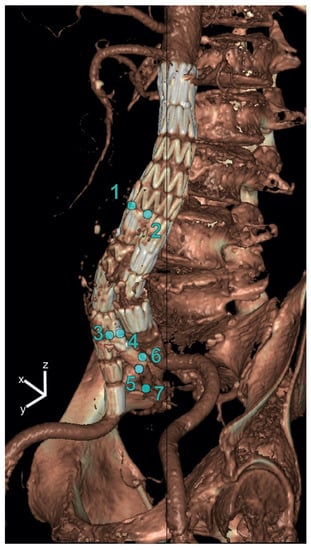

For both IBDs, displacement amplitudes in the x-(lateral), y-(anterior–posterior) and z-(craniocaudal) directions were quantified by applying the deformation fields using backward mapping to points manually selected on the static CT volume. For each point, the pathlength during the cardiac cycle was calculated as well, i.e., the sum of the traveled distances of a point on the IBD between the subsequent phases of a cardiac cycle. The following seven points were selected: the bifurcation of the EVAR main graft (Points 1 and 2), the IBD flow divider (Points 3 and 4), the distal markers of the IIA component (5 and 6) and the first bifurcation of the IIA (7) (see Figure 1).

Figure 1. Selected points on the iliac branched device for displacement analysis in x-(lateral), y-(anterior–posterior) and z-(craniocaudal) directions. The points were selected at the bifurcation of the main graft (Points 1 and 2), the IBD flow divider (Points 3 and 4), the distal markers of the IIA component (Points 5 and 6) and the first bifurcation of the IIA (Point 7).